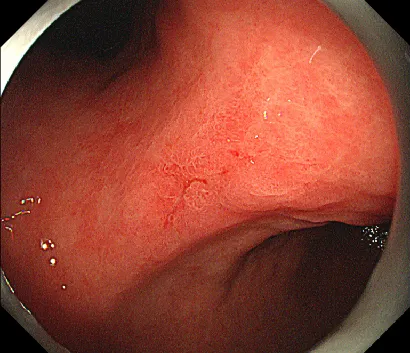

病例简介:林某,男,71岁,主诉:腹部隐痛不适8月余。胃镜胃角中央见一浅表隆起,中凹陷0-IIa+IIc)病变,大小约1.2cm×1.0cm,表面发红

11:23开始:左侧卧位操作。早癌病灶在2cm以内,萎缩背景,发红色调,ⅡC为主,分化型肿瘤可能性偏大,注意是否为混合性肿瘤,牵手型胃癌;这种病灶标记要标到肿瘤边界8-10mm左右,可以沿裂隙周边隆起做标记,把隆起部分都包进去活检一周内行ESD剥离影响不大2周后再行ESD会有纤维化形成,剥离难度会加大